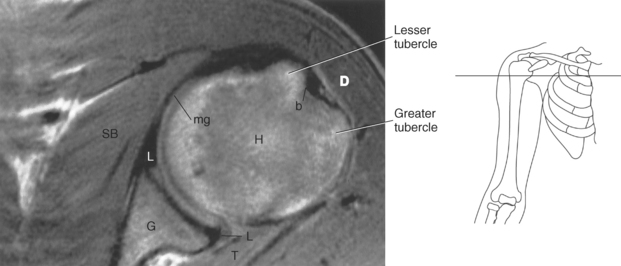

Figure 9.27 Axial, T1-weighted MR scan of shoulder.

Key: c, Clavicle; cc, coracoclavicular ligament; CP, coracoid process; ch, coracohumeral ligament; D, deltoid muscle; H, humeral head; SB, subscapularis muscle; SS, supraspinatus muscle; G, glenoid fossa; L, labrum; ss, supraspinatus tendon; b, tendon of long head of biceps muscle; IG, inferior glenohumeral ligament; mg, middle glenohumeral ligament; sb, subscapularis tendon; T, teres minor muscle.